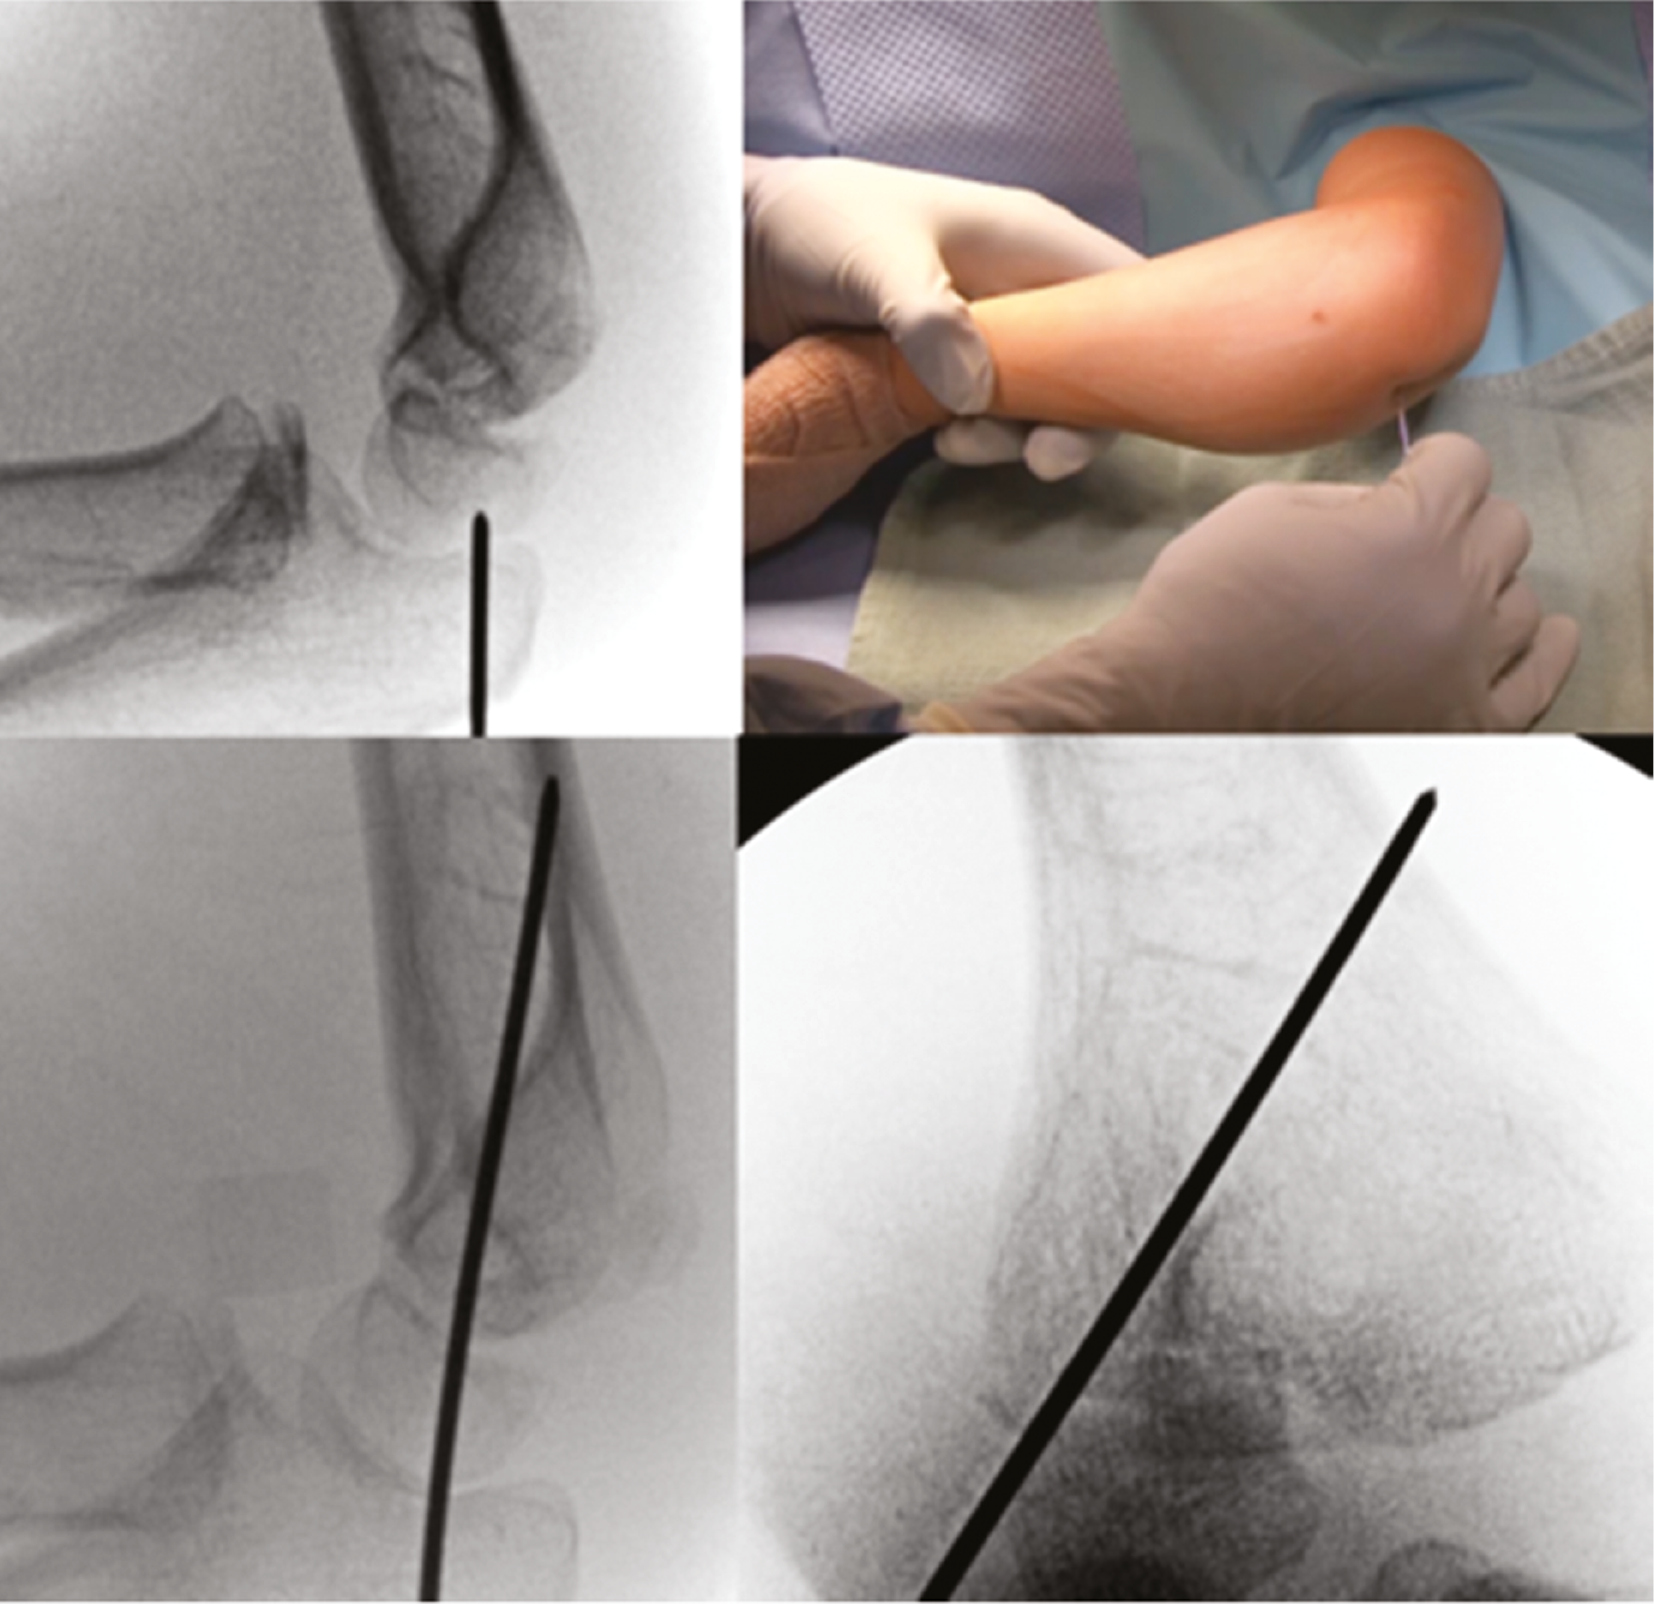

Operative Technique: The patient is prepped and draped with an extremity drape to expose up to the shoulder. An attempt at a closed reduction can be performed utilizing elbow varus and forearm pronation to disengage the fragments followed by supination and elbow valgus.4 Direct pressure with the surgeon’s thumb can improve the reduction (Figures 4–7).

Figure 4. A minimally displaced lateral fracture is partially reduced with thumb pressure.

Figure 5. A single K-wire is used to provisionally fix lateral condyle fracture.

Figure 6. Further compression can be obtained by using a cannulated depth gauge over the K-wire.

Figure 7. A second wire is divergently placed to prevent displacement, and a third wire will be placed to finalize reduction.